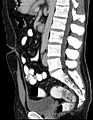

Vertical section of bladder, penis, and urethra. Urachus is seen at top